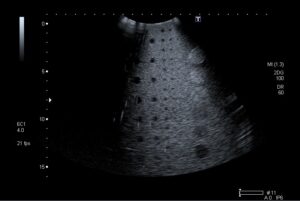

Avant réparation

Image avant réparation des cristaux